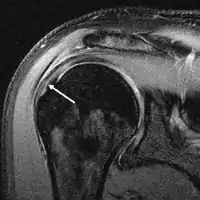

Diagnostic modalities, dependent on circumstances, include X-ray, MRI, MR arthrography, double-contrast arthrography, and ultrasound. Although MR arthrography is currently considered the gold standard, ultrasound may be most cost-effective.[31] Usually, a tear will be undetected by X-ray, although bone spurs, which can impinge upon the rotator cuff tendons, may be visible.[32] Such spurs suggest chronic severe rotator cuff disease. Double-contrast arthrography involves injecting contrast dye into the shoulder joint to detect leakage out of the injured rotator cuff[33] and its value is influenced by the experience of the operator. The most common diagnostic tool is magnetic resonance imaging (MRI), which can sometimes indicate the size of the tear, as well as its location within the tendon. Furthermore, MRI enables the detection or exclusion of complete rotator cuff tears with reasonable accuracy and is also suitable to diagnose other pathologies of the shoulder joint.[34]

MRI

Magnetic resonance imaging (MRI) and ultrasound[42] are comparable in efficacy and helpful in diagnosis although both have a false positive rate of 15 - 20%.[43] MRI can reliably detect most full-thickness tears although very small pinpoint tears may be missed. In such situations, an MRI combined with an injection of contrast material, an MR-arthrogram, may help to confirm the diagnosis. It should be realized that a normal MRI cannot fully rule out a small tear (a false negative) while partial-thickness tears are not as reliably detected.[44] While MRI is sensitive in identifying tendon degeneration (tendinopathy), it may not reliably distinguish between a degenerative tendon and a partially torn tendon. Again, magnetic resonance arthrography can improve the differentiation.[44] An overall sensitivity of 91% (9% false negative rate) has been reported indicating that magnetic resonance arthrography is reliable in the detection of partial-thickness rotator cuff tears.[44] However, its routine use is not advised, since it involves entering the joint with a needle with potential risk of infection. Consequently, the test is reserved for cases in which the diagnosis remains unclear.